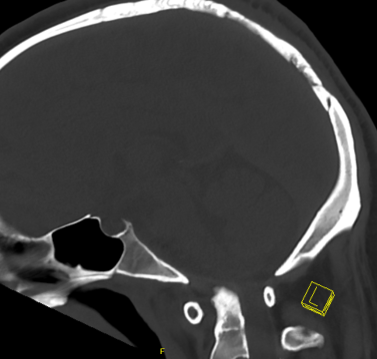

CT

MRI

| Type IV | Bony dislocation | C1/C2 bony fusion on CT | 4 (<0.5%) |

Trans-oral anterior osseous decompression Posterior fusion |